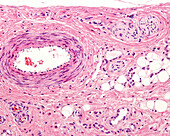

13952291 - Artery and vein, light micrograph

13613505 - Arteriole and venule, light micrograph

13613463 - Small blood vessels, light micrograph